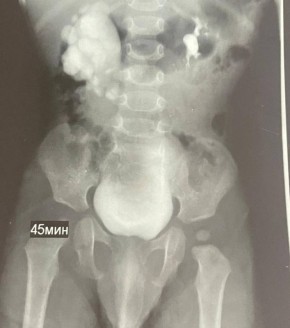

Патологию заметили ещё во время беременности мамы малыша, а сразу после его рождения специалисты взяли ребенка под наблюдение. Весной 2025 года обследование показало: у мальчика — гидронефроз. При этом заболевании почка...

У ребёнка ещё до рождения заметили проблемы с почкой на УЗИ, а после появления на свет состояние стало ухудшаться — диагностировали гидронефроз. При этом опасном состоянии почка могла бы перестать функционировать.В ноябре врачи ставропольской больницы...